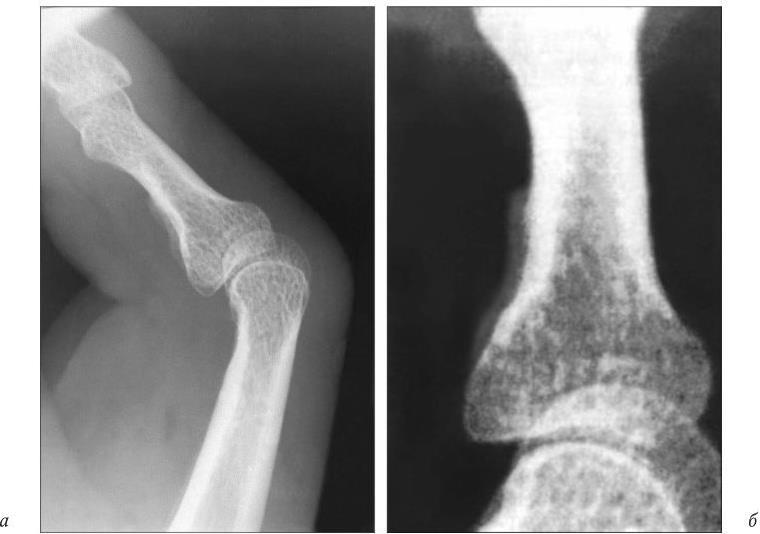

Диагноз периартрита может быть подтвержден рентгенологически. На рентгенограммах, лучше при микрофокусной рентгенографии с прямым увеличением изображения (наиболее отчетливо при трехкратном усилении), можно выявить отек мягких тканей в области инсерции сухожилия, а также неравномерное разрастание периоста там же (рис. 27).

Рис. 27. Рентгенограмма IV пальца правой кисти больного с контрактурой Дюпюитрена. 4-кратное увеличение рентгеновского изображения:

а — виден отек мягких тканей и контрактура. Неравномерное разрастание периоста в области инсерции сухожилия; б — деталь рентгенограммы. Более отчетливо представлено разрастание периоста